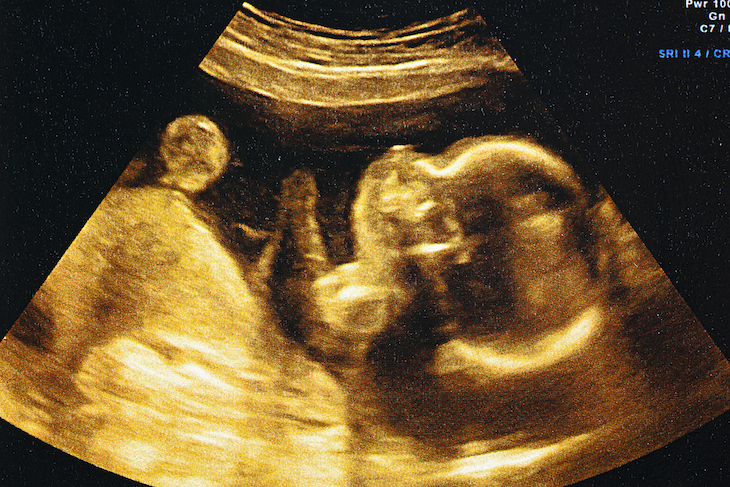

(Photo: iStock)

The womb, that secretive house of early life, is coming under the spotlight. For a long time it was scarcely mentioned in public at all, save in obstetrics, gynaecology, DH Lawrence novels and the Bible. In recent years, however, the uterus has attracted the dubious attentions of the ‘wellness’ industry: Gwyneth Paltrow even recommended ‘cleansing’ it by sitting over a machine pumping out ‘mugwort steam’. And now a new book by the writer and midwife Leah Hazard – Womb: The Inside Story of Where We All Began – looks at this shape-shifting organ from all angles: medical, emotional, political and futuristic. What emerges from her examination is fascinating, contentious, and potentially chilling – as she looks ahead to a future in which the womb, as we understand it, may gradually become redundant.